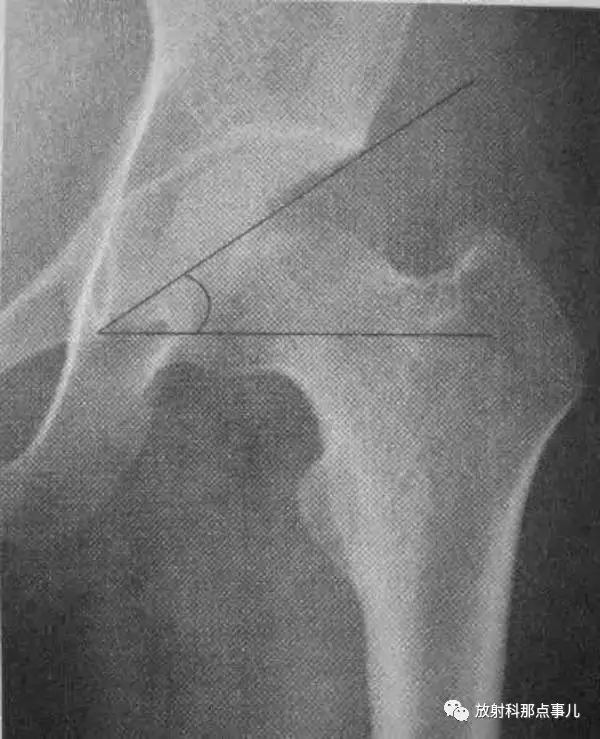

Kline线

沿股骨颈上缘划线并沿股骨头方向的延长线。正常此线应该切割部分股骨头骨骺,若骨骺位于该线内侧,提示股骨头骨骺向下滑脱。